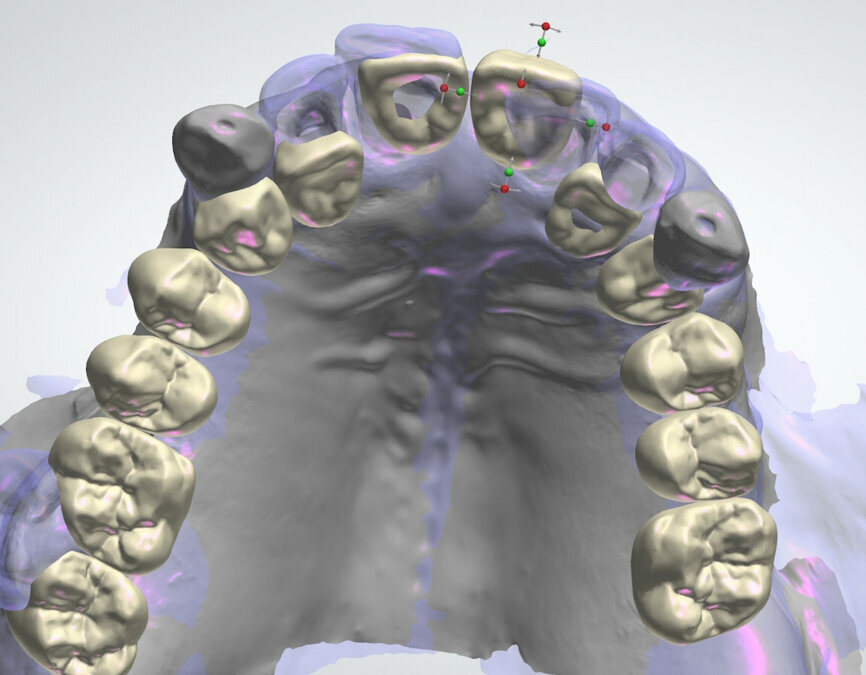

On receipt of the scan body file (File 2), the laboratory imported it into 3Shape’s Dental System and created a virtual model, matching the virtual SRA scan bodies from Straumann’s original library with the intra-oral SRA scan bodies (Figs. 13 & 14). A working file was created for designing the temporary prosthetic emergence profile for the SRA.

To perform the design of the temporary full-arch prosthesis and maintain (or modify) the vertical dimension of occlusion and occlusion, the patient’s pre-preparation study model scan file (File 1) was imported as a pre-preparation scan (blue) and merged with the implant file scan (File 2), using the preserved teeth present on both scans. The software allowed us to mark the same points on the preserved teeth on both files, the study model scan and the implant scan (both contained the preserved teeth). Thus, the laboratory was able to work on a single file containing both Files 1 and 2, merged by means of the preserved teeth. Designing the temporary prosthesis is an easy task using the image of the patient’s own teeth as a mock to be copied (Fig. 15). Any design modification can easily be done (Figs. 16 & 17).